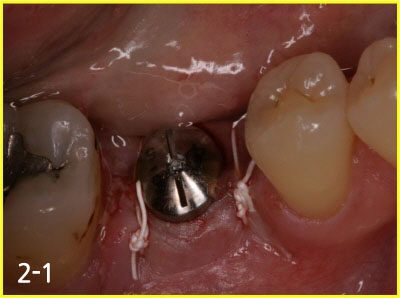

Performing implant placement and bone graft